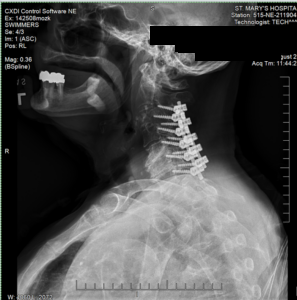

EMS rushed our client to the emergency room at St. Mary’s Hospital. Doctors ordered X-rays, which showed a major fracture of her femur near the hip, and an MRI of her neck showed a severe spinal cord compression:

She underwent multiple major procedures, including:

- Cervical spine decompression and fusion surgery